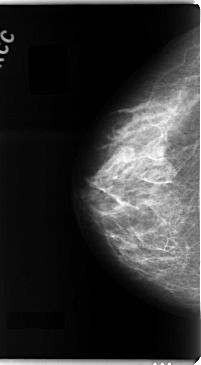

C_0097_1.LEFT_CC

LEFT_CC LINES 4728 PIXELS_PER_LINE 2640 BITS_PER_PIXEL 12 RESOLUTION 50 OVERLAY